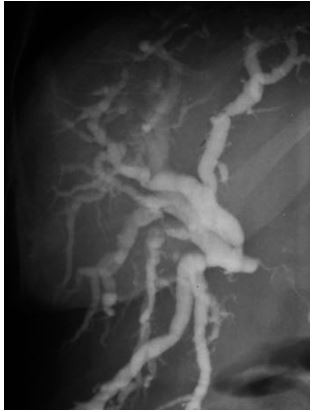

A imagem a seguir é de uma colangiopancreatografia endoscópica retrógrada. Este exame poderia pertencer a todos os pacientes abaixo, EXCETO UM:

Homem, 38 anos, portador de retocolite ulcerativa, com aumento de fosfatase alcalina, p-ANCA positivo.

Mulher, 48 anos, com trombose portal crônica e transformação cavernomatosa, há 2 anos com aumento de enzimas hepáticas canaliculares.

Homem, 62 anos, com icterícia, anticorpo antinuclear positivo, hipergamaglobulinemia (às custas de IgG-4), sem retocolite ulcerativa.

Mulher, 64 anos, com aumento de fosfatase alcalina e anticorpo antinuclear positivo com pontos isolados, anticorpo antimitocôndria negativo.